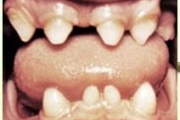

Kaasasündinud hammaste puudumine

Hambaanomaaliad